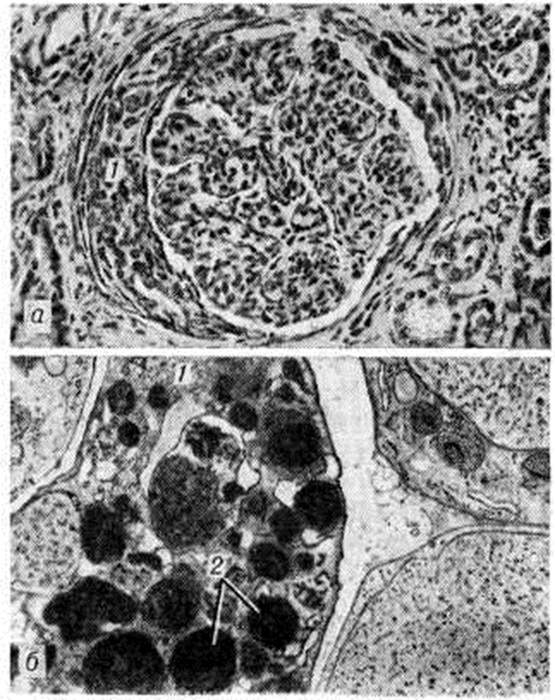

Рис. 2.

Микропрепарат (б) и электронограмма (а) почки при пролиферативном гломерулонефрите: а — в просвете клубочкового капилляра (1) гранулоцит (2); за базальной мембраной (3) эндотелия (4) видны цитоплазматические отростки пролиферирующих мезангиальных клеток (5), окружённые мембраноподобным веществом; ×13 500; б — гистологическая картина пролиферативного гломерулонефрита, значительное увеличение количества ядер эндотелия капилляров клубочка (окраска гематоксилин-эозином).

При пролиферативном Гломерулонефрит, развитие которого обычно связано с воздействием стрептококка, пролиферация эндотелиоцитов и мезангиоцитов, как правило, сочетается с экссудативными изменениями, инфильтрацией клубочка полиморфно-ядерными лейкоцитами. Отслаивая эндотелий, лейкоциты проникают к базальной мембране капилляров и мигрируют в мезангии (рисунок 2). Их постоянно можно найти рядом с гранулярными субэпителиальными депозитами в виде горбов («humps»), содержащими гетерологичные иммунные комплексы, в состав которых входят стрептококк, иммуноглобулин и комплемент.

При электронной микроскопии депозиты иммунных комплексов обнаруживаются в биопсионном материале из почки через 2—4 недель от начала заболевания, но встречаются через 6 недель и более. С лейкотаксическим эффектом комплемента этих комплексов связана инфильтрация клубочка лейкоцитами, развитие иммунного воспаления в его соединительной ткани — мезангии. Повреждения базальной мембраны клубочковых капилляров также обусловлены литическим действием комплемента иммунных комплексов и лизосомальных ферментов лейкоцитов. В результате повреждения базальной мембраны и процессов внутрисосудистой коагуляции в капиллярах клубочков образуются тромбы, а также наблюдается реактивная пролиферация клеток клубочка. Пролиферация эндотелиоцитов сочетается с расширением мезангия, связанным с увеличением количества мезангиоцитов и накоплением мембраноподобного материала — мезангиального матрикса, что характерно для пролиферативного интракапиллярного диффузного Гломерулонефрит (мезангиопролиферативный Гломерулонефрит). Клинической, проявления интракапиллярного Гломерулонефрит различны, однако безусловна определённая зависимость между гематурией и выраженностью пролиферативной гломерулярной реакции.